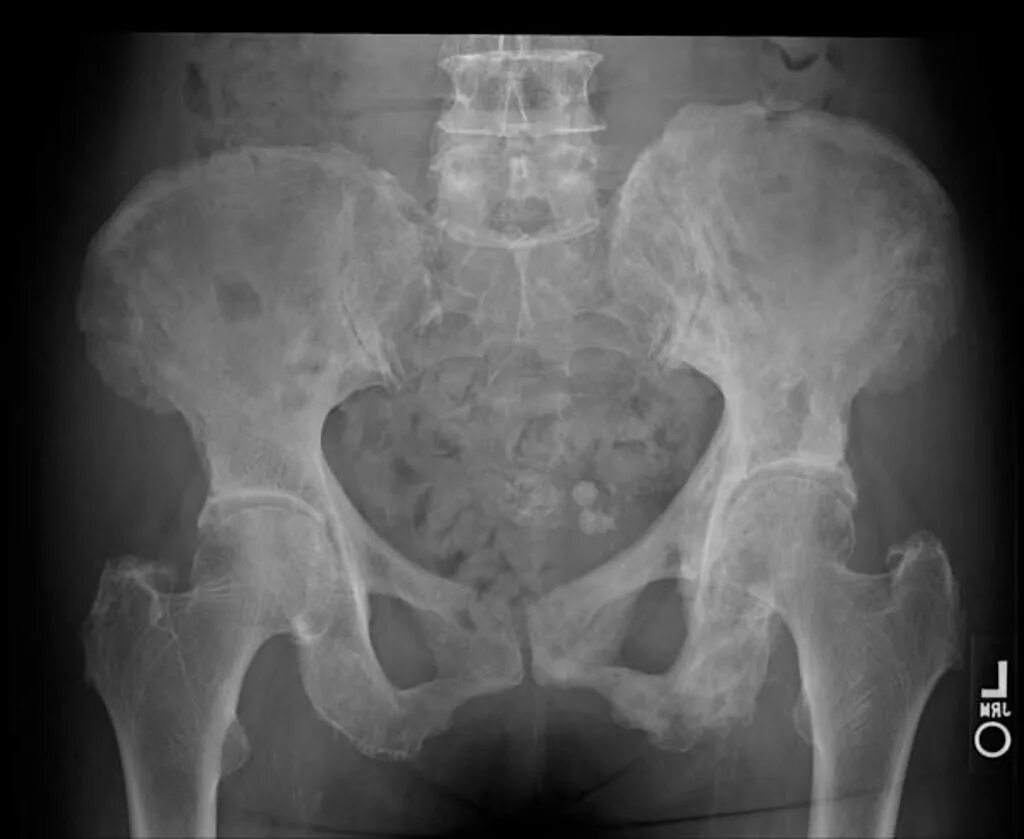

Метастазы в крестце